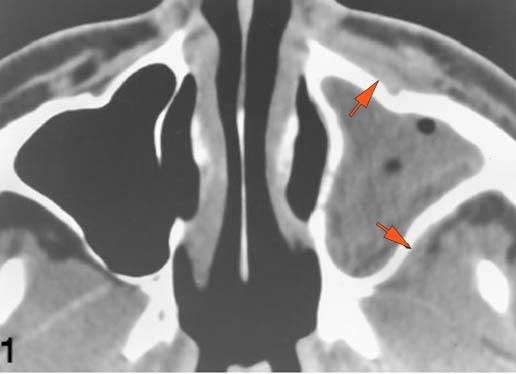

There is a subperiosteal abscess or edema along the medial wall, roof or floor of the orbit. [Yes/No]